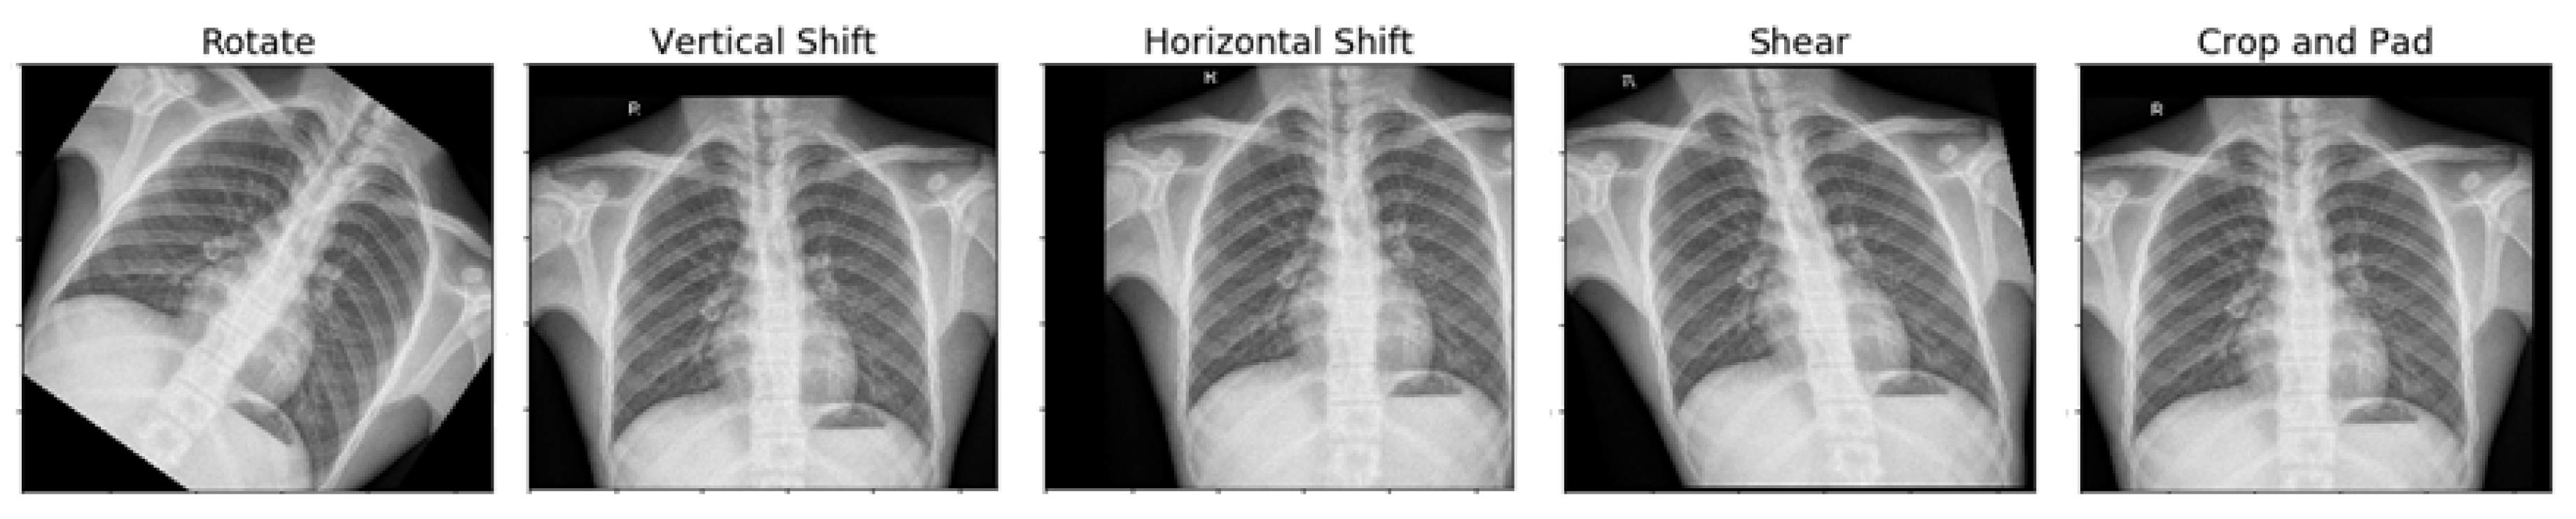

The settings utilized in image augmentation are shown below in Table 2. The images after performing various augmentation techniques are shown below (Figure 4). Only one of these techniques was used to generate the augmented image.

Figure 4.

Resultant image after performing the augmentation technique.